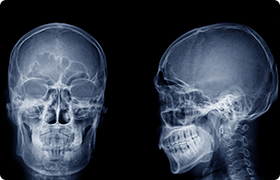

精確な診断と丁寧な説明

先端機器を駆使した精密検査で

理想の歯並びを実現します

矯正治療専用のレントゲン撮影装置「セファログラム」、あごの関節まで立体的に把握できる「歯科用CT」、印象材を使わずスキャニングで歯型を採取できる「iTero」などを用いて得た情報を基に、綿密な治療計画を立案し、患者様へわかりやすくご説明いたします。

セファログラム

歯科用CT